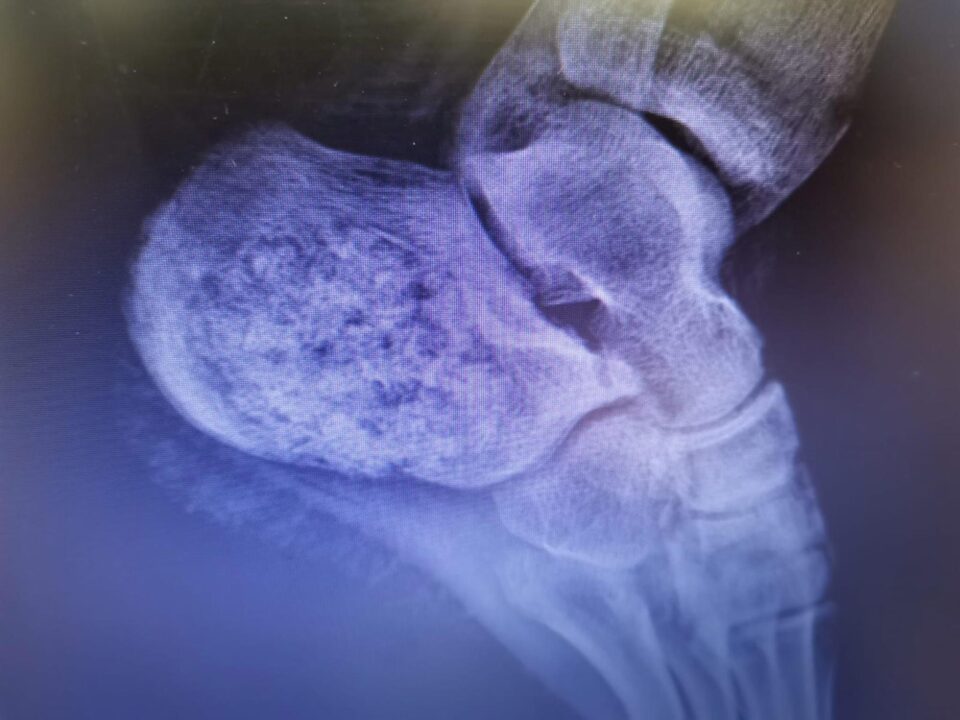

Un caz de tumoră la nivelul unui nerv, extrem de rar întâlnită, a fost diagnosticată și tratată cu succes de medicii de la Spitalul Județean de Urgență „Sf. Ioan cel Nou” Suceava, care a devenit astfel al șaselea spital din lume în care a fost diagnosticată o astfel de formațiune. Purtătorul de cuvânt al spitalului, dr. Dan Teodorovici, a arătat că pacienta în vârstă de 20 de ani a fost diagnosticată, în urmă cu aproximativ o lună, cu o formațiune tumorală numită schwannom sau neurinom, care provoca măcinarea osului la nivelul călcâiului stâng, cuprinzând aproape în totalitate osul calcaneu. Doctorul Răzvan Codrin Bandac, șeful secției Ortopedie a Spitalului de Urgență Suceava, a declarat că acest caz este deosebit deoarece este vorba despre o tumoră extrem de rară, care a produs un grad ridicat de distrugere osoasă. Acest lucru a necesitat reconstrucția osului cu transplant de os uman, cu care a fost corectat defectul rezultat după îndepărtarea țesutului tumoral.

Dr. Bandac a explicat că intervenția chirurgicală a decurs în doi timpi, inițial practicându-se îndepărtarea marginală a tumorii, în urmă cu 3 săptămâni, și efectuarea de către medicii anatomo-patologi, dr. Andreea Botezan și dr. Luminița Miron, a examenului histopatologic. Acest lucru a permis diagnosticarea rapida a unui schwannom intraosos, o tumoră benignă a nervului periferic, excepțional localizată la acest nivel.

„În literatura de specialitate sunt citate numai 5 cazuri de acest fel”, a subliniat dr. Bandac.

În a doua etapă a intervenției chirurgicale, care a avut loc în ziua de 14 decembrie a.c., s-a realizat reconstrucția calcaneului stâng prin umplerea defectului osos cu transplant de os uman, importat de la Banca de Țesuturi Colentina București, cu sprijinul medicului coordonator al Băncii de Țesuturi, dr. Andrei Nica. Potrivit doctorului Bandac, pacienta evoluează normal postoperator și urmează a fi externată. Ea va avea glezna și piciorul stâng imobilizate timp de 6 săptămâni și se va putea sprijini pe acest picior după 3 luni de la intervenție.

„Particularitatea acestui caz o reprezintă atât raritatea leziunii, ca frecvență și determinare tisulară, dar și efortul echipei medicale de a diagnostica și trata în timp record, în aproximativ 3 săptămâni, o leziune tumorală cu potențial de agravare rapidă și severă, care netratată în timp util ar fi produs colapsul osos prin fracturarea spontană a calcaneului, urmat de un deficit funcțional major, la o pacientă cu vârsta foarte tânară”, a declarat dr. Bandac.

Acesta a mai spus că este al doilea caz tratat, cel puțin relatat de literatura de specialitate, prin reconstrucție cu alogrefă osoasă umană de la banca de țesuturi, primul caz fiind raportat în 2016 de Centrul Oncologic Hunan din China. „Celelalte trei cazuri au fost raportate în Turcia și India, în 2012, și în Brazilia, în 2020, dar cu defecte osoase mai mici, la două cazuri efectuându-se plombare cu autogrefă osoasă, de la același pacient și într-un caz prin fixare cu șuruburi și plombarea defectului osos cu ciment acrilic”, a mai spus doctorul Bandac. Intervenția s-a realizat cu anestezie rahidiană, echipa operatorie fiind alcatuită din dr. Mihai Sorin Petrasuc, dr. Ana Loredana Baitoc, medici primari ortopezi, dr. Dorin Stanescu, medic primar ATI, și asistenta de Bloc operator Ancuta Bizgan.

Tumora